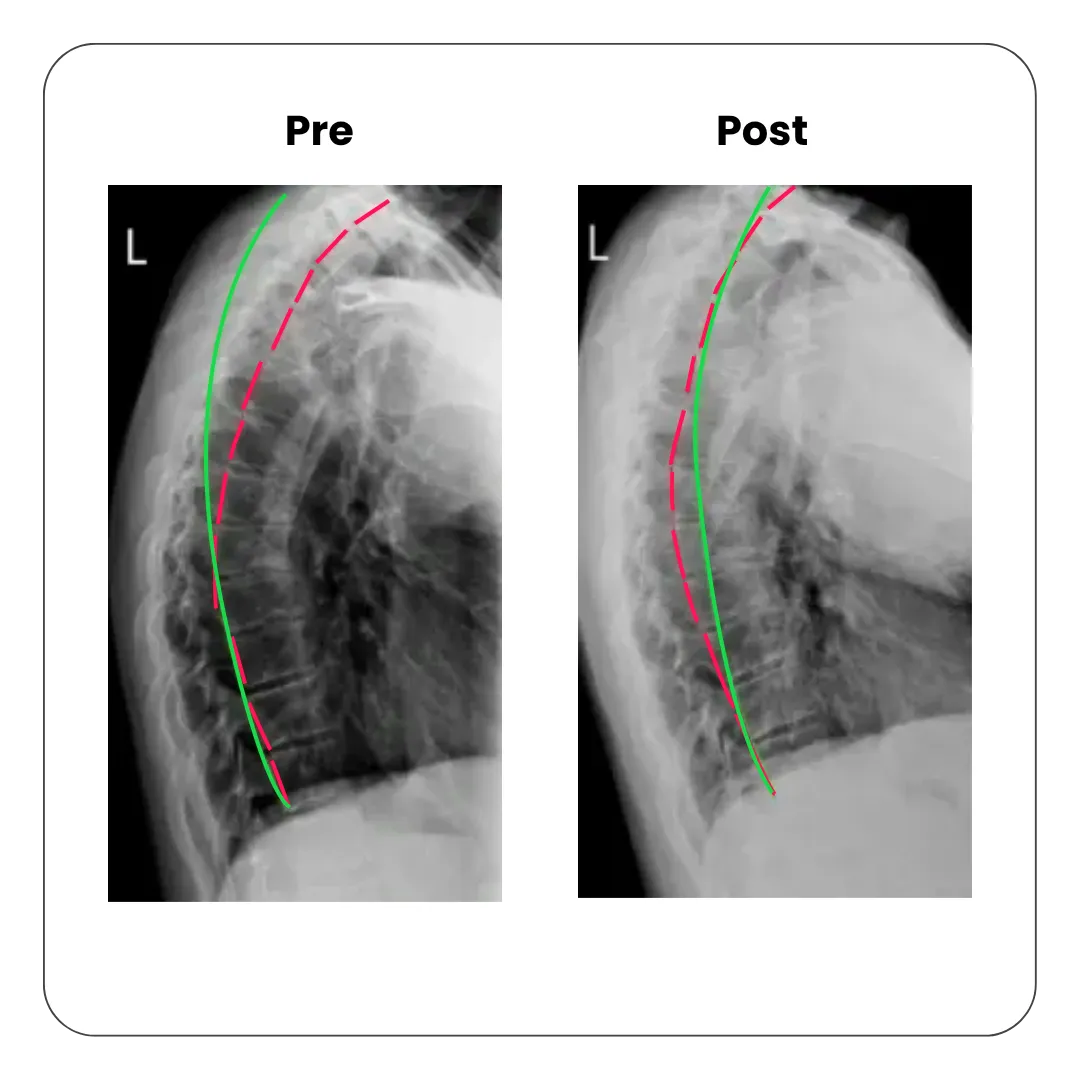

Once digital x-rays are taken, they are analyzed by PostureRay software, a state-of-the-art technology that digitally plots abnormal deviations. This allows our patients to easily see exactly what corrections are necessary and track the progress of treatment. Click here